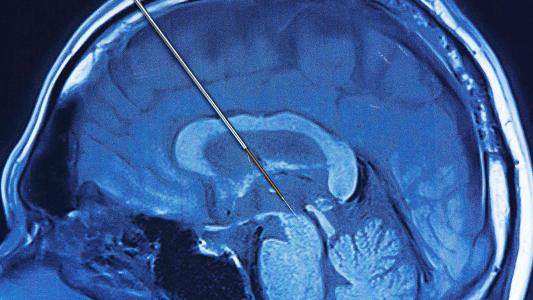

Deep brain stimulation: explained